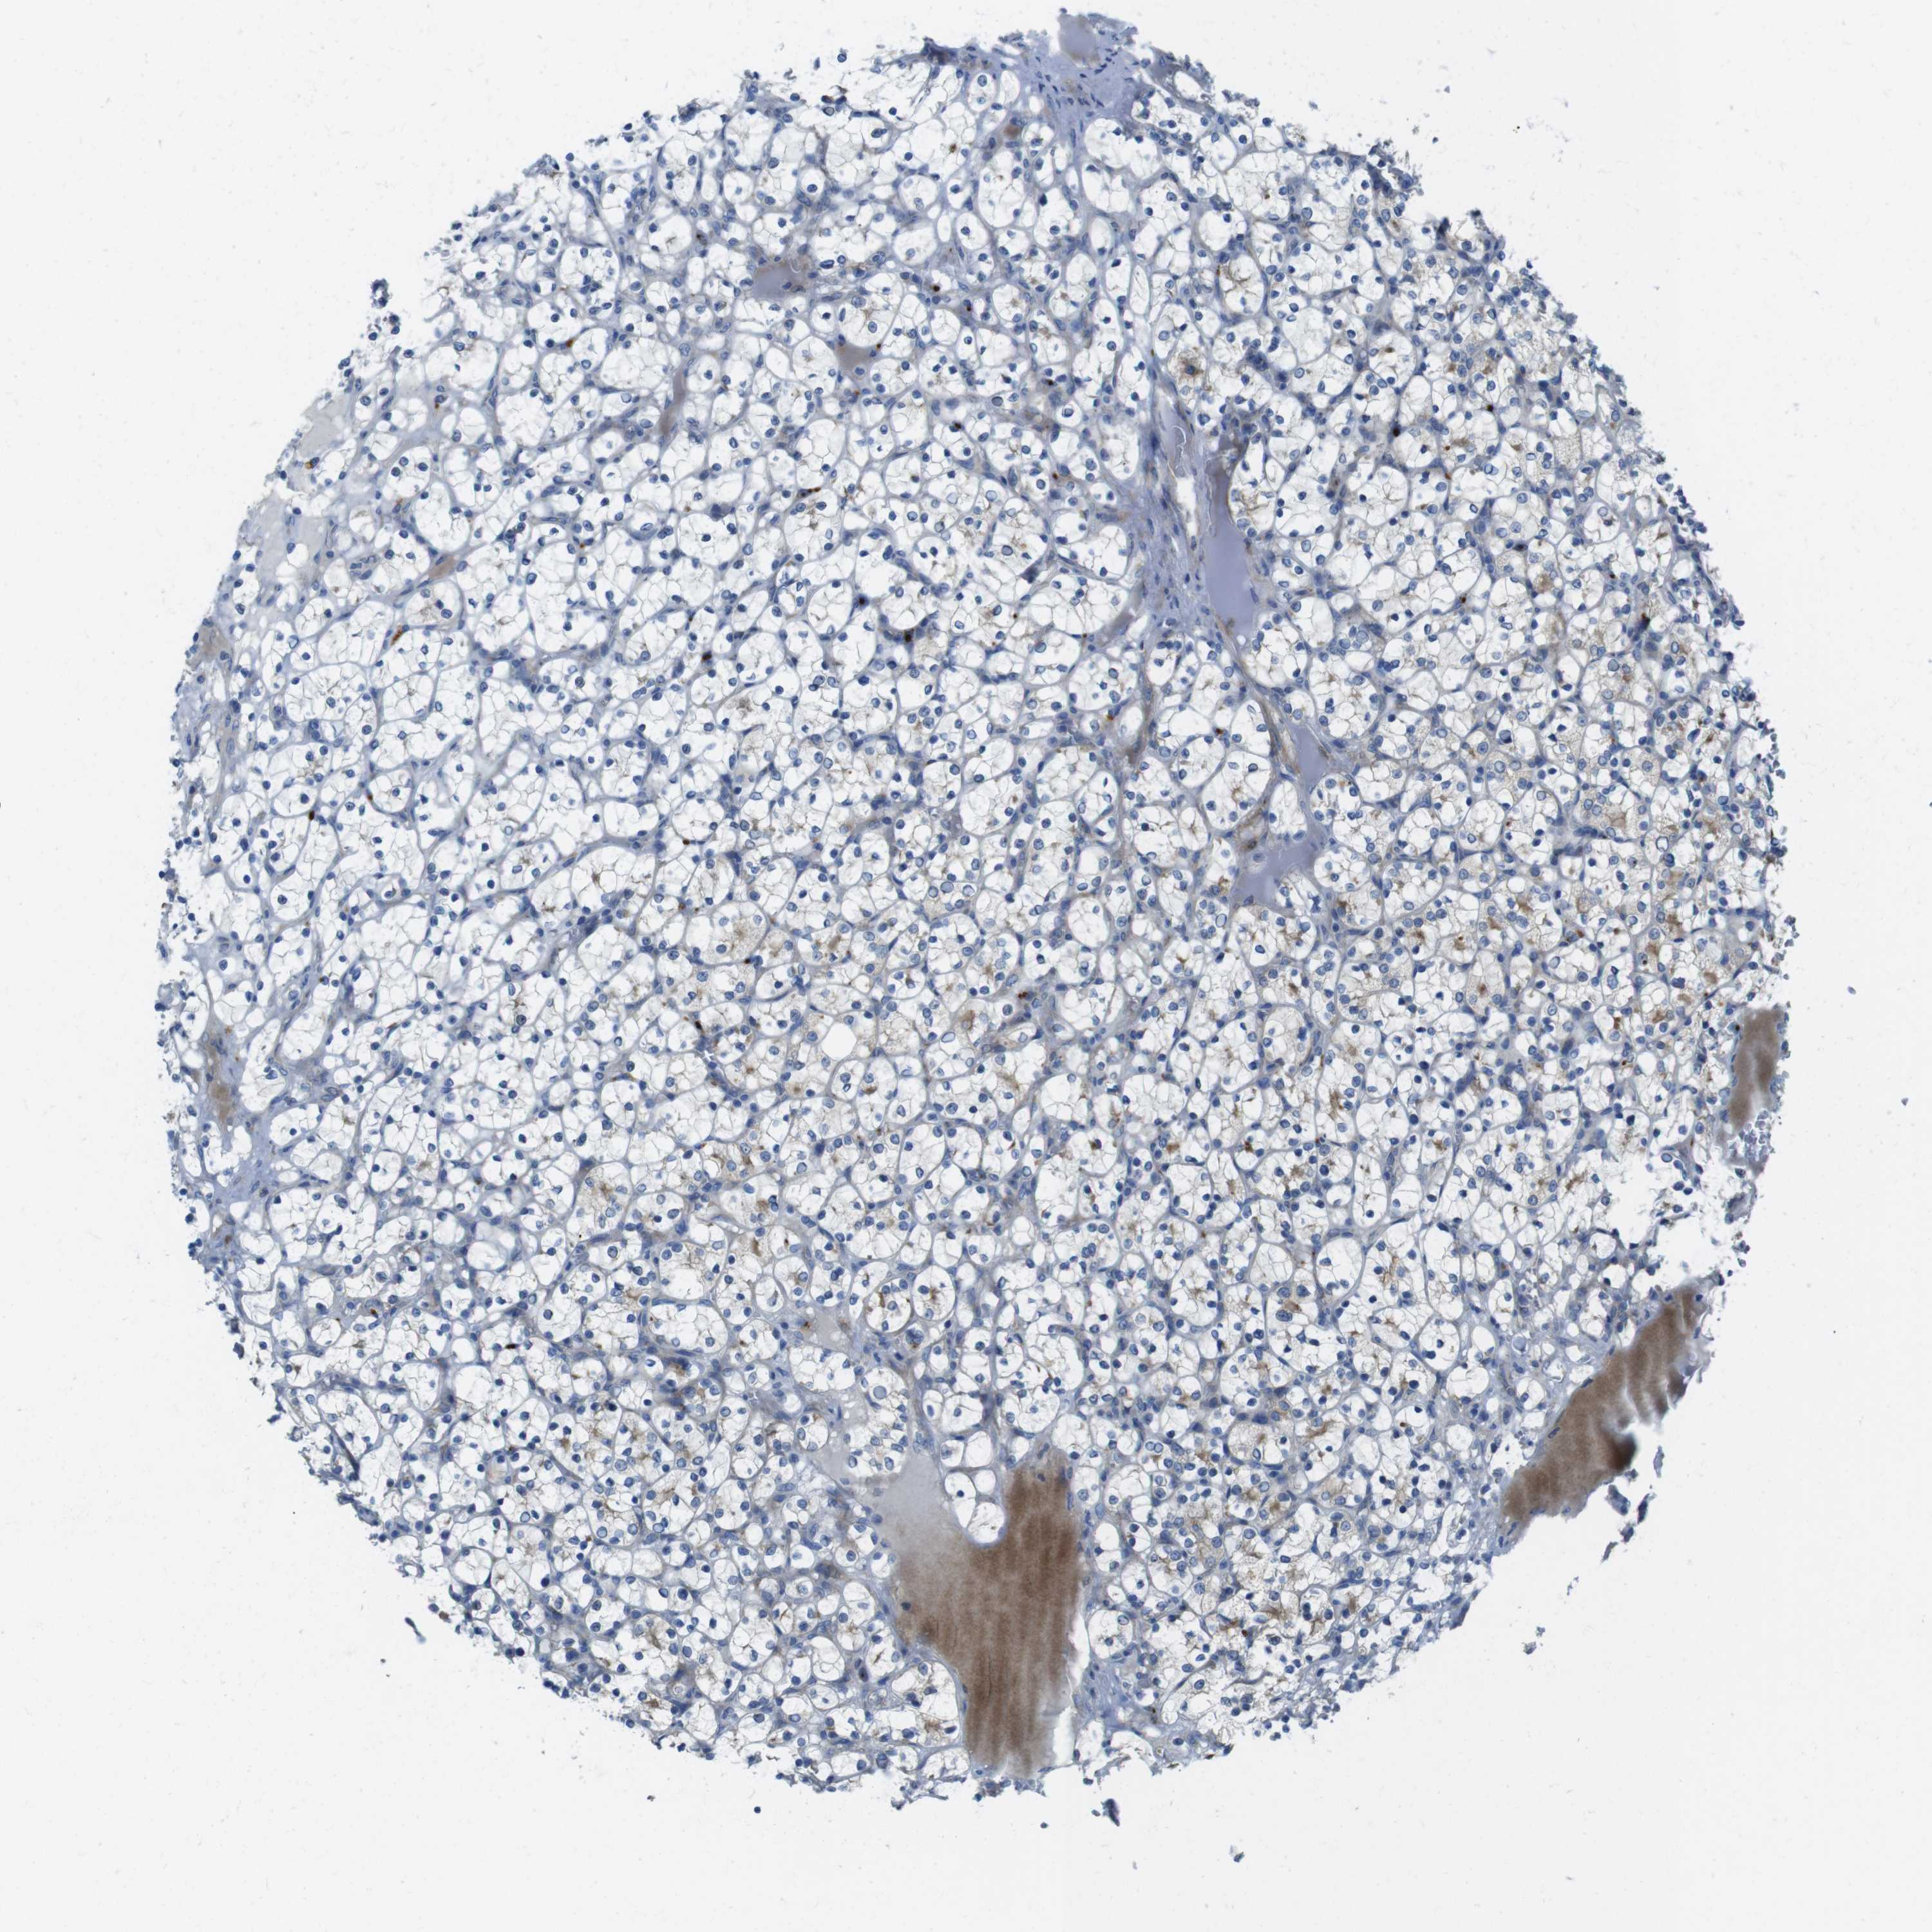

KICH TCGA KIRC TCGA KIRC VALIDATION KIRP TCGA PROTEIN RCC CPTAC PROTEIN EXPRESSION

Renal cancer

Kidney renal clear cell carcinoma

KIDNEY RENAL CLEAR CELL CARCINOMA (TCGA) - Interactive survival scatter ploti

TMEM234 is not prognostic in Kidney Renal Clear Cell Carcinoma (TCGA)

Average pTPM 10.7

Number of samples 521